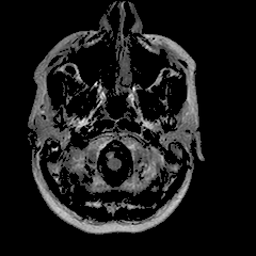

基于深度学习分割算法的 PyTorch 实现的 U-Net,用于脑部 MRI 中 FLAIR 异常区域的分割。该算法曾应用于论文《低级别胶质瘤基因组亚型与深度学习算法自动提取的形状特征之间的关联》(https://doi.org/10.1016/j.compbiomed.2019.05.002)。

用于开发和评估的数据集已在 Kaggle 上公开:kaggle.com/mateuszbuda/lgg-mri-segmentation。该数据集包含来自 TCIA LGG 收藏 的 MR 图像,并附有杜克大学认证放射科医师标注的分割掩码。